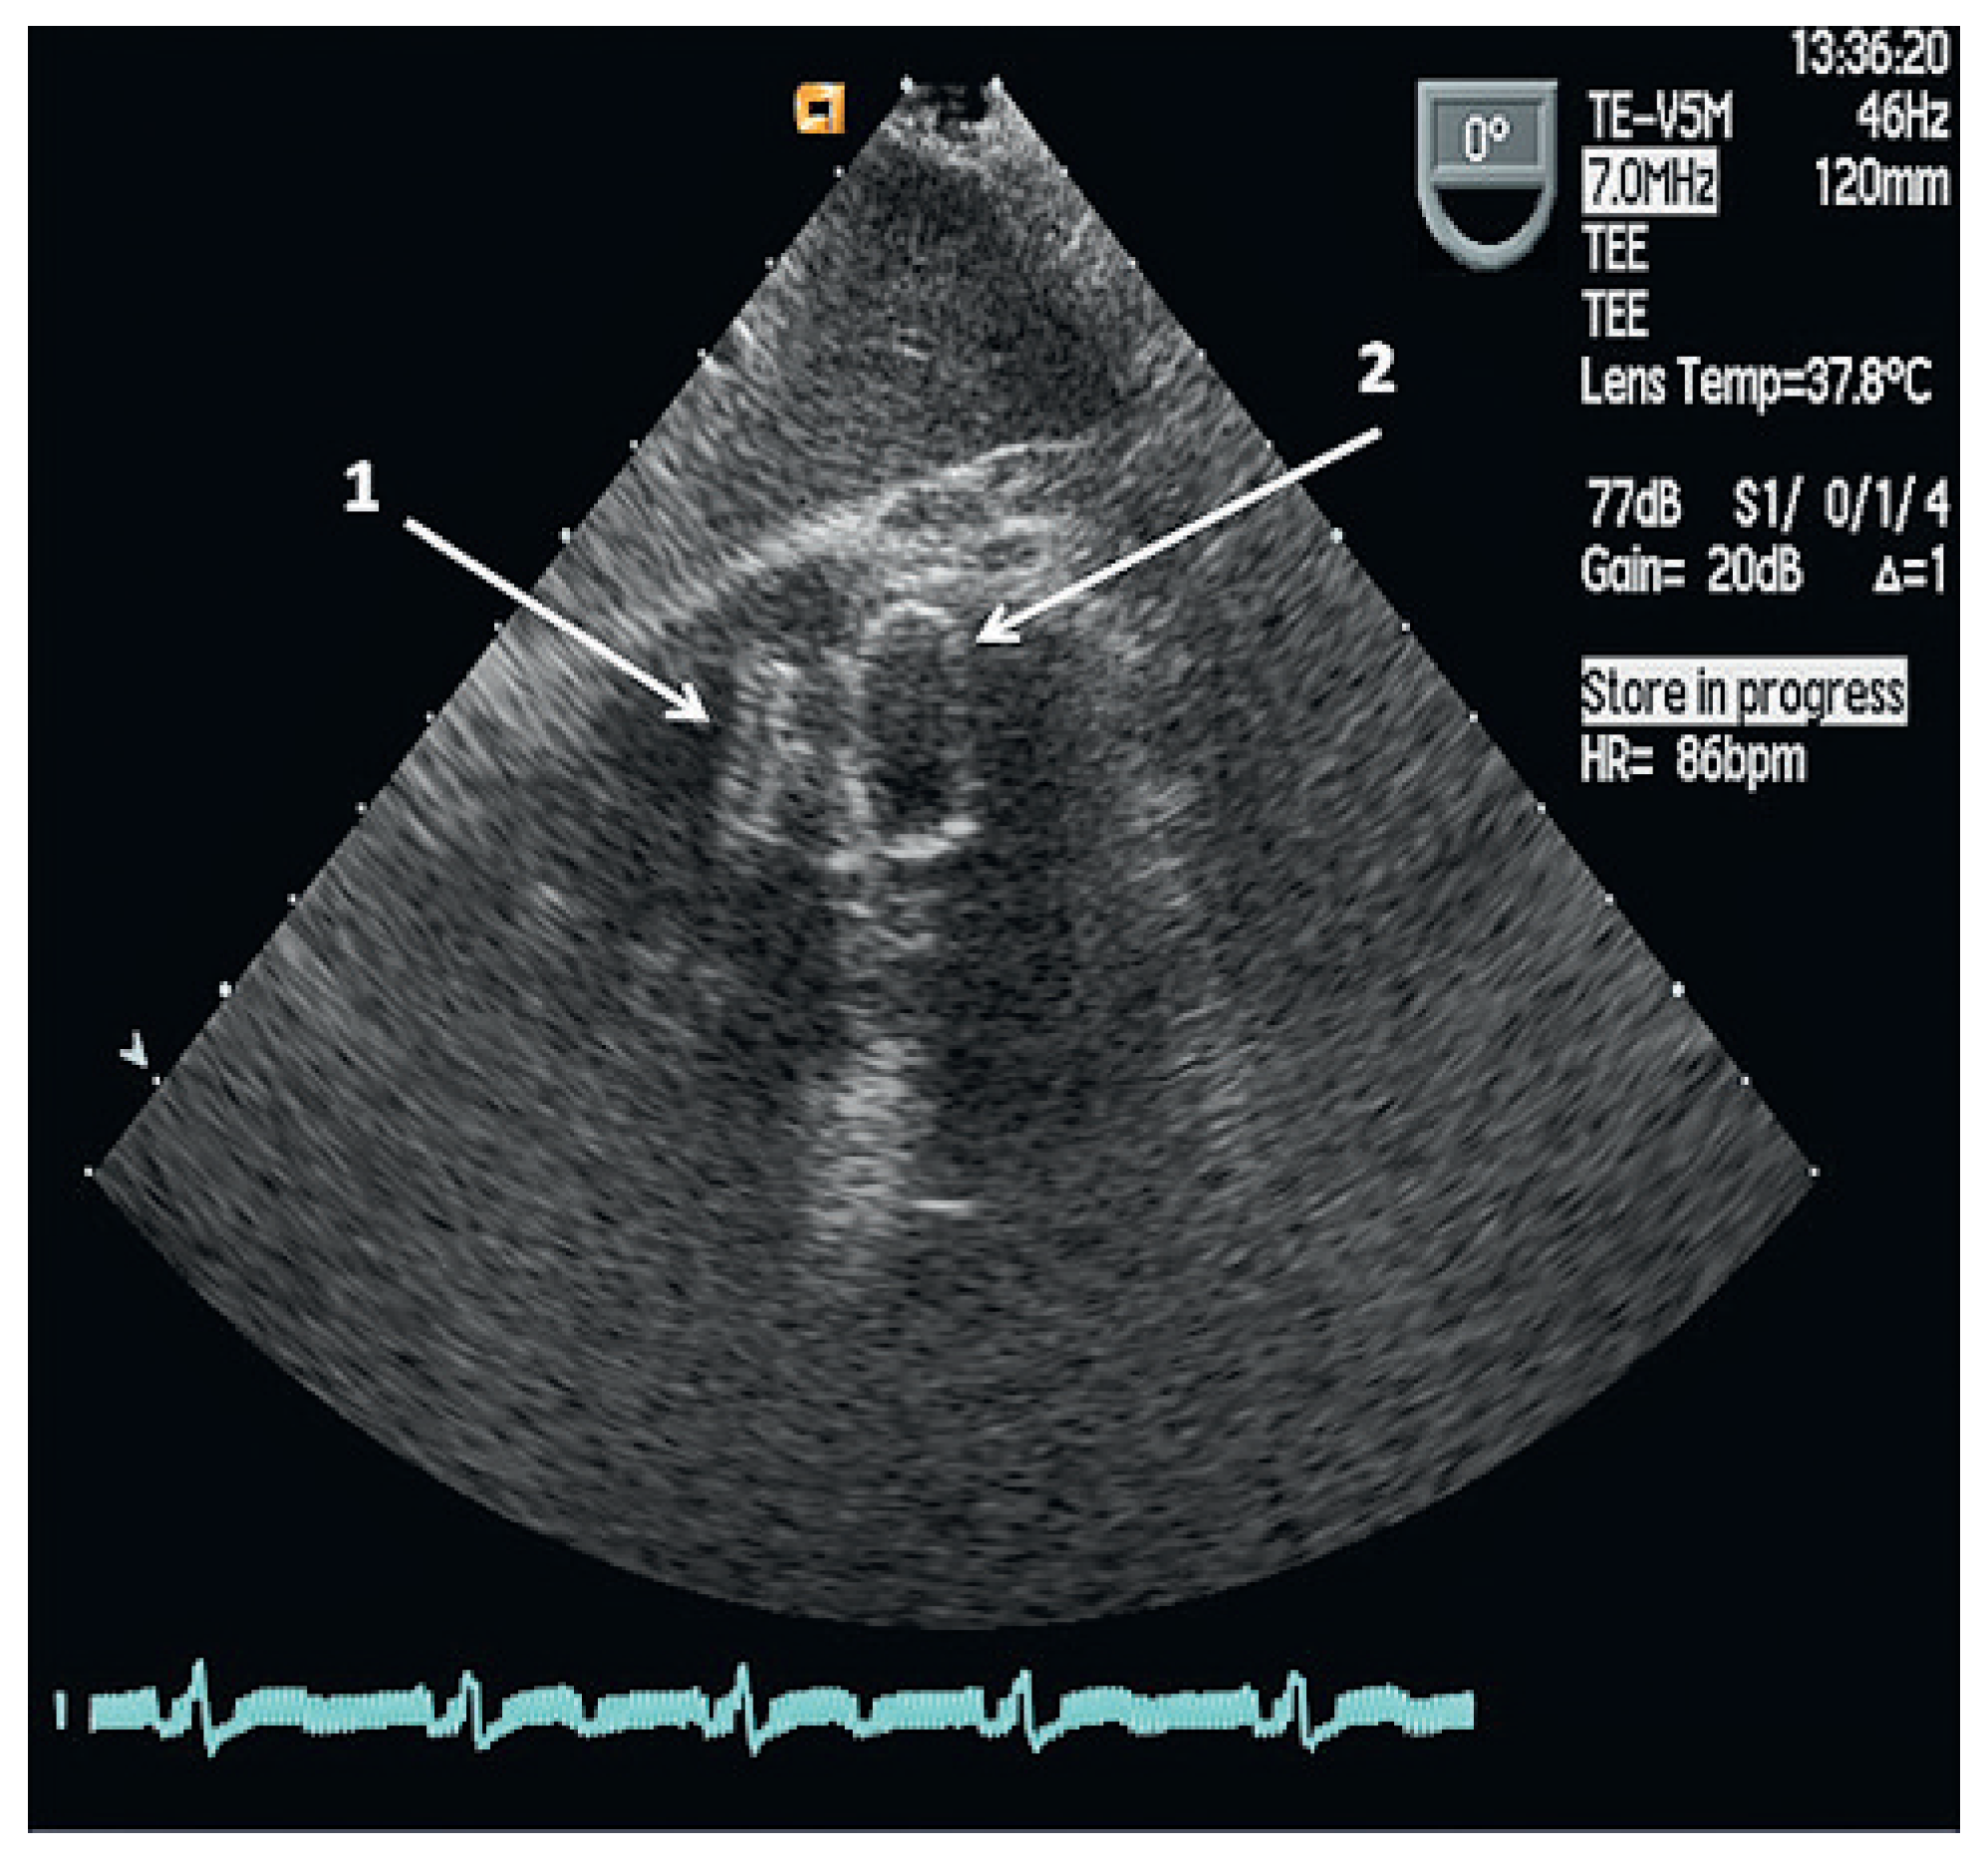

Two months after cardiac surgery the patient was readmitted with light-headedness and dizziness but had no chest pain or shortness of breath. Physical examination revealed a grade IV high pitched pansystolic heart murmur. No fever or chills were documented. Transoesophageal echocardiography (TEE) detected a residual VSD of 15 mm located at the apex with a left to right shunt, a peak instantaneous gradient of 30 mm Hg and an estimated Qp:Qs of >1.5. Left ventricular function was normal. The patient was referred for transcatheter closure of the significant residual defect.

Three months later, a follow-up TEE demonstrated no residual left-right ventricular shunt and the two VSD occluders were aligned and in stable position (Figure 4). Nine months after the last intervention the patient reported no shortness of breath and continued dual antiplatelet therapy with acetylsalicylic acid and clopidogrel.

Figure 4. Follow-up transoesophageal echocardiogram performed six months after the initial and three months after the additional transcatheter closures of the VSD showing two devices.